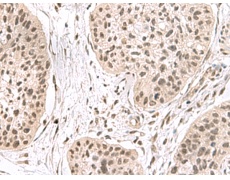

IHC positive control: |

Human esophagus cancer |